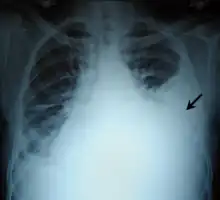

Chest X-ray showing left sided hemothorax (arrowed)